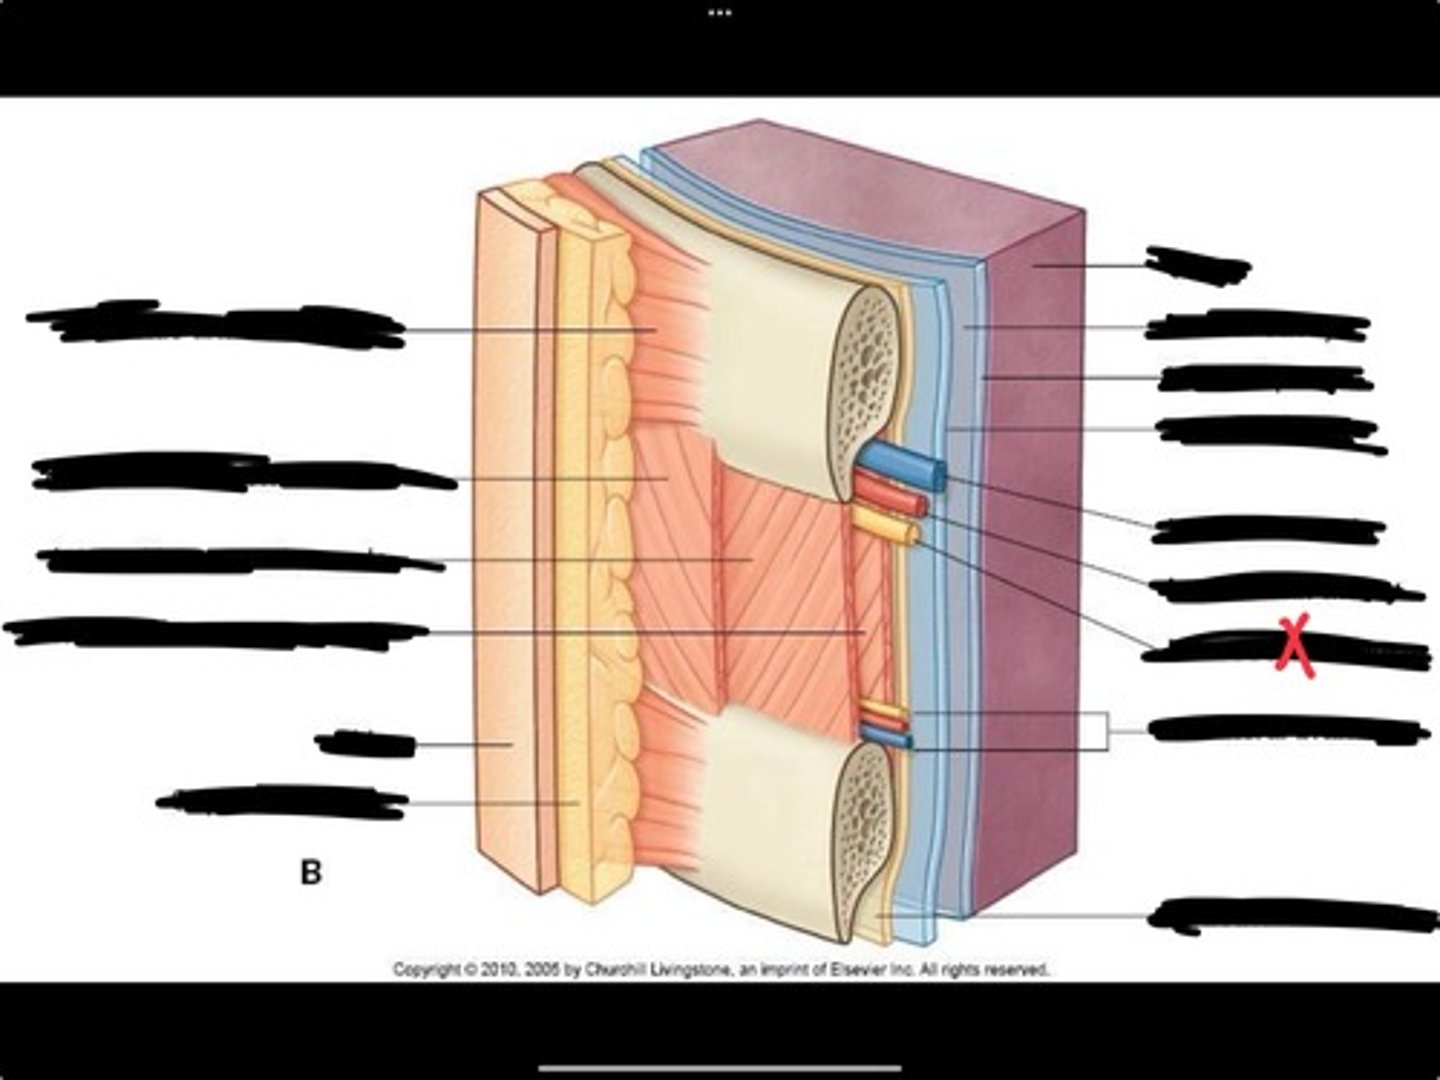

Innermost intercostal muscle

Skin

Internal intercostal muscle

External intercostal muscle

Serratus anterior muscle

Lung

Pleural cavity

Visceral pleura

Parietal cavity

Intercostal vein

Intercostal artery

Collateral branches

Intercostal nerve

Endothoracic fascia

Diaphragm